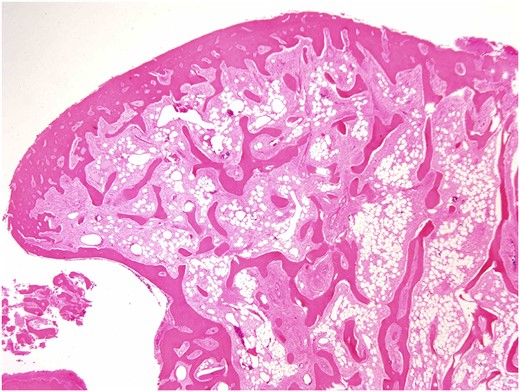

Both specimens showed identical histopathological features, being composed of chronically inflamed nasal mucosa undermined and compressed by sharply demarcated, zonated, multilobulated osseous proliferation without any cartilaginous component. The core and bulk of the lesions was composed of anastomosing, cancellous type bony trabeculae separated by fibrofatty marrow spaces, surfaced by denser cortical type bone, features characteristic of benign osteoma (Figs 2 and 3).

Osteoma, low-magnification photomicrograph. Low-magnification image of a protuberant bosselation emphasizing the bony zonation and total lack of haematopoietic marrow. There is neither significant osteoblastic activity nor appreciable osteoclasis (H&E stain, original magnification ×1.25).